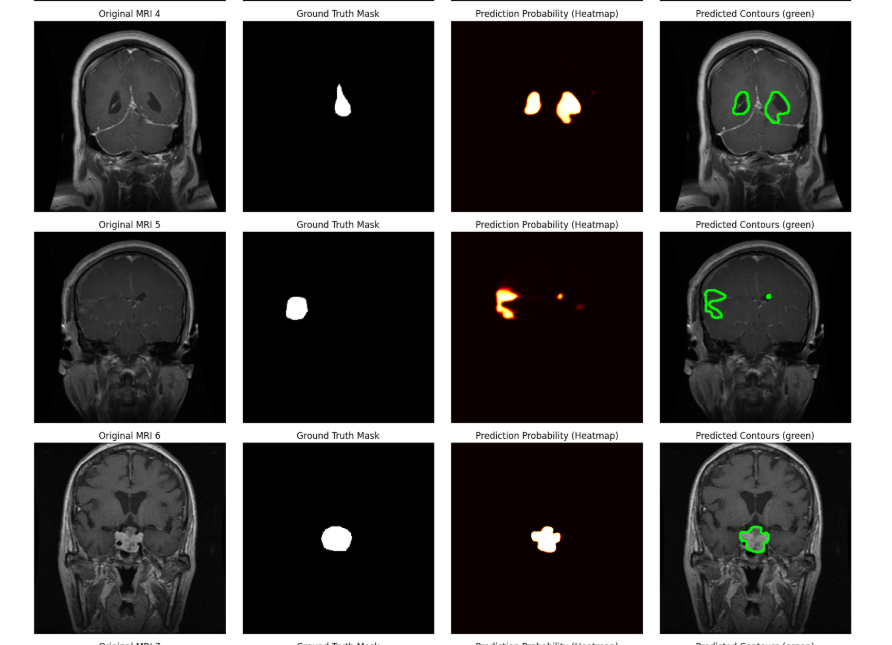

I provide advanced Computer Vision solutions for complex image and video-based projects.This service is ideal for businesses, research, and academic projects that require accurate and well-optimized...